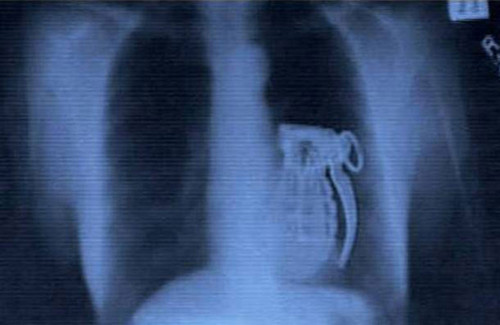

Hình ảnh khủng khiếp này thuộc về một tay khủng bố. Anh ta tìm cách nuốt chửng quả lựu đạn song không thể kích nổ nó.